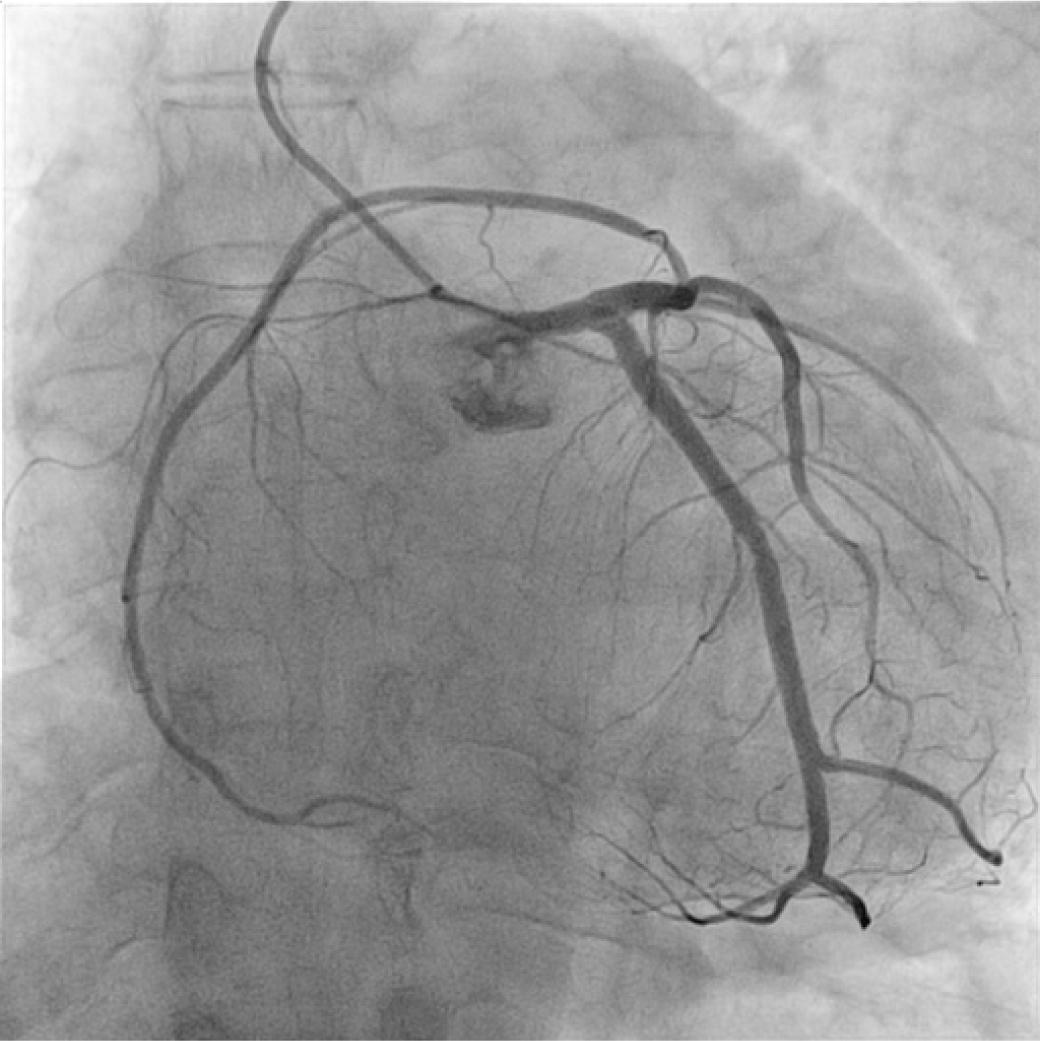

Twenty-nine percent of the patients had significant coronary artery disease (figure 2). Most of the patients had no coronary lesions (58%). The most common coronary artery anomalies were the anomalous origin of left circumflex artery from the right coronary artery (38.71%) (figure 3) and the anomalous origin of right coronary artery from right coronary sinus of Valsalva (19.35%) (table 2) and the least common was anomalous origin of RCA from the LAD (0.017%) (figure 5). Eight (25.8%) patients underwent coronary revascularization by percutaneous coronary intervention (7 patients − 22.58%) or coronary artery bypass grafting (1 patient − 3.22%). No death or significant complication were recorded in the 31 patients during the 5 years follow-up.

Anomalous origin of right coronary artery from the left anterior descending artery.

| Anomalous origin of RCA from the LAD | 1 | 0.017% | |